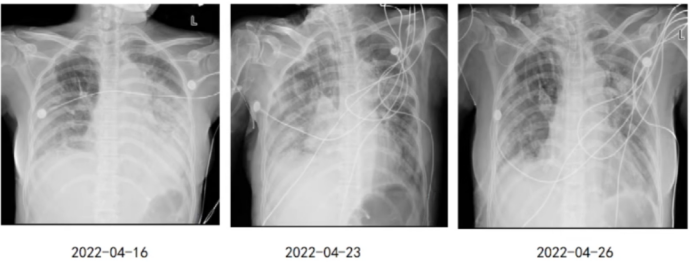

4月23日气管切开后复查胸部X线片,右侧感染有好转迹象,4月26日,感染明显好转(图2)

图片

图2  患者插管前后胸部X线片变化